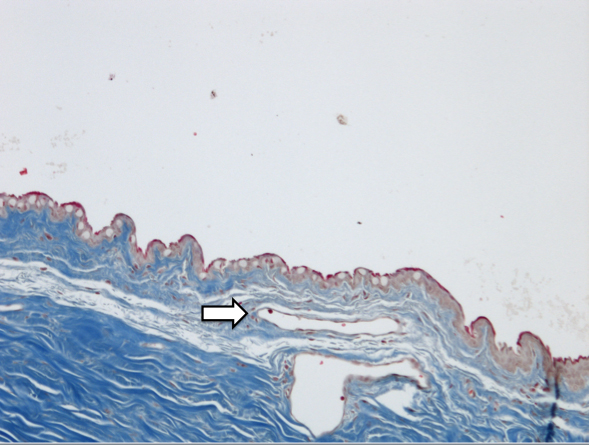

Figure 3 of SooHoo, Mol Vis 2012; 18:714-719.

Figure 3. Histologic analysis of bleb tissue revealed less collagen deposition with Masson Trichrome stain compared to the BSS control as well as a thin capsule (white arrow) at the location of the Ozurdex® implant (10× magnification).